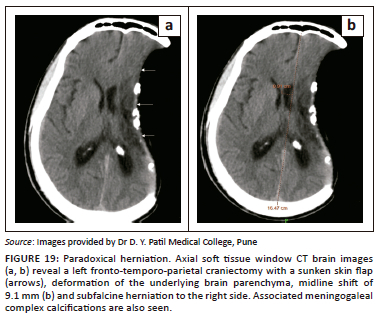

Paradoxical herniation

Paradoxical herniation is a rare, late complication in the post-craniectomy patient. It is characterised by a sunken skin flap and contralateral displacement and herniation of brain, with resultant mass effect, midline shift and effacement of CSF spaces (Figure 19 and Figure 20).20 The mechanism is usually a decrease in intracranial pressure because of lumbar puncture, ventricular drainage or ventriculoperitoneal shunting, which leads to an imbalance in the intracranial pressure and the atmospheric pressure. It is a potentially life-threatening condition, usually treated by clamping any shunts or drains, putting the patient in the Trendelenberg position, administering fluids and performing an early cranioplasty.22